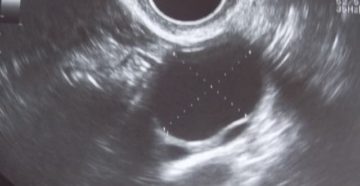

Киста на правом яичнике у женщин: симптомы и лечение образования Киста правого яичника является доброкачественной…